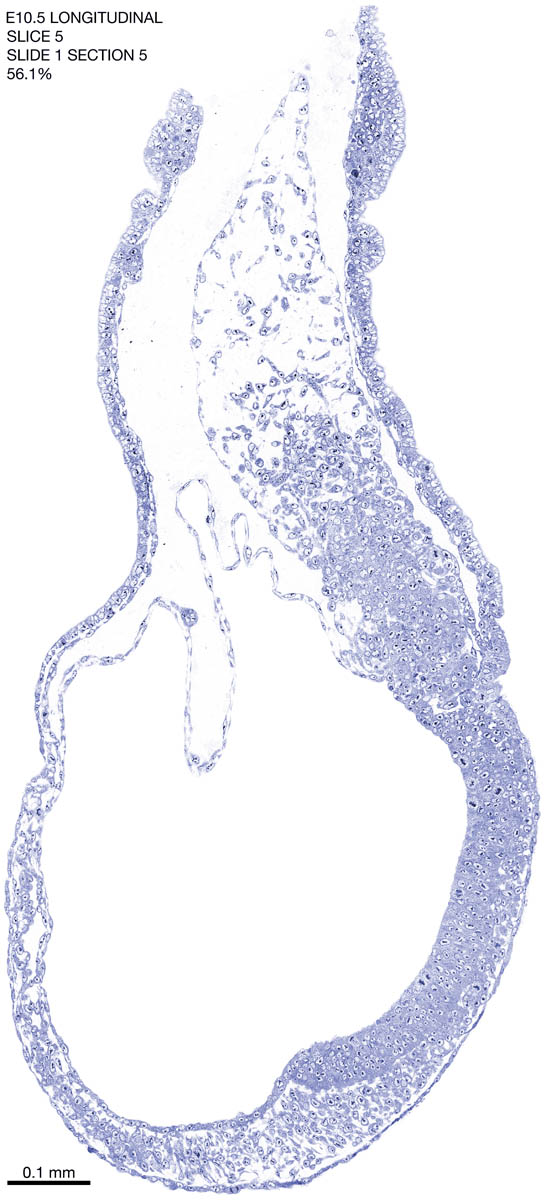

E10.5 Longitudianal Archive This page contains jpg files of ALL SLICES (each 3µm thick) that were scanned of the E10.5 longitudinally cut specimen. Download: Large | High Res Download: Large | High Res Download: Large | High Res Download: Large | High Res Download: Large | High Res Download: Large | High Res Download: Large | High Res Download: Large | High Res Download: Large | High Res Download: Large | High Res Download: Large | High Res Download: Large | High Res Download: Large | High Res Download: Large | High Res Download: Large | High Res Download: Large | High Res Download: Large | High Res Download: Large | High Res Download: Large | High Res Download: Large | High Res Download: Large | High Res Download: Large | High Res Download: Large | High Res Download: Large | High Res Download: Large | High Res Download: Large | High Res Download: Large | High Res Download: Large | High Res Download: Large | High Res Download: Large | High Res Download: Large | High Res Download: Large | High Res Download: Large | High Res Download: Large | High Res Download: Large | High Res Download: Large | High Res Download: Large | High Res Download: Large | High Res Download: Large | High Res Download: Large | High Res Download: Large | High Res Download: Large | High Res Download: Large | High Res Download: Large | High Res Download: Large | High Res Download: Large | High Res Download: Large | High Res Download: Large | High Res Download: Large | High Res Download: Large | High Res Download: Large | High Res Download: Large | High Res Download: Large | High Res Download: Large | High Res Download: Large | High Res Download: Large | High Res Download: Large | High Res Download: Large | High Res